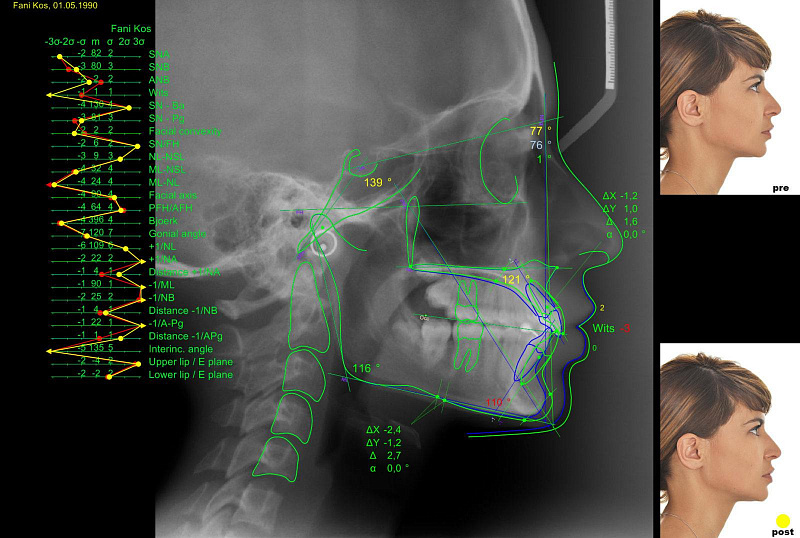

ТРГ (телерентгенография) – это рентгенологическое исследование черепа в боковой проекции с строго фиксированного расстояния. Это «золотой стандарт» диагностики в ортодонтии и челюстно-лицевой хирургии. Снимок ТРГ позволяет оценить не просто зубы, а скелетную структуру черепа, соотношение челюстей, их размеры и положение относительно друг друга и основания черепа. На основе ТРГ врач проводит точные расчеты (цефалометрический анализ), что необходимо для планирования лечения брекетами, элайнерами, хирургических операций и протезирования.

4. Анализ и планирование. Ключевой этап! Полученный снимок анализирует лечащий врач-ортодонт клиники «Крона Дент». С помощью специальной компьютерной программы врач проводит детальный цефалометрический анализ: наносит ключевые точки, измеряет углы и расстояния, ставит точный диагноз и, что самое важное, составляет подробный и индивидуальный план лечения. На основе ТРГ моделируется будущее положение зубов и челюстей.

На боковом ТРГ-снимке врач видит не просто «череп в профиль», а набор четких контуров:

· Костные структуры: основание черепа, контуры верхней и нижней челюсти, скуловые кости, носовые кости.

· Положение зубов: визуализируются коронки и корни всех зубов, их наклон.

· Мягкие ткани профиля: контур носа, губ, подбородка, что важно для эстетического прогнозирования.

· ВНЧС (косвенно): видно суставное пространство и положение головки нижней челюсти.

После разметки точек врач получает числовые значения углов и линейных размеров, которые объективно характеризуют тип лица, патологию прикуса и позволяют выбрать оптимальный метод лечения.